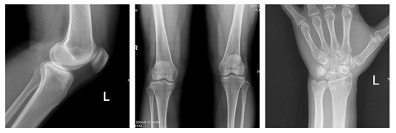

在医疗设备领域,一款优秀的医疗设备往往需要大量对临床的深入洞察,在技术创新突破之外,基于临床的设计创新往往更能满足临床的应用需求。而临床的需求往往是多种复杂场景下的综合,腾灵在贴合临床的基础之上不断进行产品设计,可实现全科室应用包括常规的X线拍片、消化道检查、骨科检查、妇科、儿科检查等等。在影像质控标准建设上,腾灵支持SID大范围可调节,满足不同部位的影像质控摄片要求。为了满足临床多角度摄片要求,腾灵的球管运动设计支持角度可调节。考虑到患者的上下床便利性与安全性问题,腾灵在床体设计上不断进行突破,目前在床体高度上已经做到业内最佳。在摆位摄片的效率性上,腾灵设计电动360°可旋转脚踏板,满足在立位状态下的正侧位高效率摄片。而在安全性的设计上,腾灵设计了首个床式可移除式滤线栅,能够有效满足儿科等特定场景的低剂量摄影要求。而包括可升降操控台设计,支持医生床旁操作等,一系列贴合临床的功能设计,让腾灵在临床多场景应用中应对自如。

图2 一机多能,全能发展